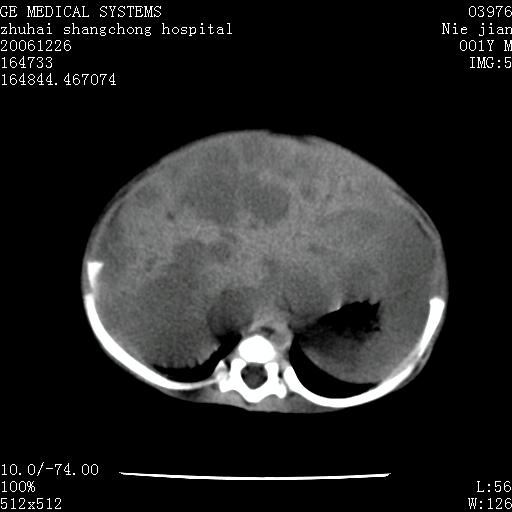

3个月婴儿腹胀来看。

肝各叶比率失调,明显增大,实质内大量脂肪侵润。另:左侧肾上腺区较大类圆形低密度肿块,左肾明显受压 下移。多考虑:1 左侧肾上腺神经母细胞瘤!2 肝弥漫性损伤!

肝各叶比率失调,明显增大,实质内见多发团块状低密度灶。另:左侧肾上腺区较大类圆形肿块,左肾明显受压 下移。多考虑:1 左侧肾上腺神经母细胞瘤!2 肝脏多发转移!

鉴别诊断:肾母细胞瘤,好发1-3岁,肾母细胞瘤是发生在肾脏,又称肾胚瘤,肾脏本身增大。而神经母细胞瘤也称成神经细胞瘤,好发1-2岁,多发生在肾上腺髓质。肾脏本身表现受压向下移位。

【影像特征】

1、肝明显增大,肝弥漫性低密度灶。

2、肾上腺区见类圆形肿块,其内密度不均,见片状偏高密度。

【诊断】

1、肝弥漫性病变,考虑急性肝炎致广泛脂肪浸润可能性大。

2、肾上腺区占位,假性肿瘤?肾上腺血肿(感染所致)?

1、关键着眼点:肝脏弥漫性病变内有没有走形的血管,仔细看部分低密度内有血管影(要有增强扫描作为证据就好了),说明并非肿瘤样病变,而是脂肪浸润。即可能不是转移瘤或原发肿瘤,低密度的形态上看,是片状,也不像肿瘤。

2、儿童肝炎最常见的是感染,有时食入性损害或药物也可致肝脏炎症,肝炎致大空泡型脂肪变性,是一种无痛性疾病,无症状,病因有营养异常、代谢性疾病、药物及病毒感染。所以脂肪变性与感染有关。

3、肝炎的结局是肝硬化,而恰恰一年后复查,已有肝硬化表现。肿瘤一般那会消失,那叫奇迹。

4、肾上腺出血也可见于败血症及感染,通常包块在数周内消失,ct表现包块内有偏高密度,可能是亚急性血肿的表现。假性肿瘤即腹部肠管积液、扩张血管及邻近结构的伪像。自然会消失。

5、因此,感染可以贯穿一切,解释一切。肿瘤自然消退?可能吗?那些应要无道理的创造奇迹的事情会那么容易发生吗?